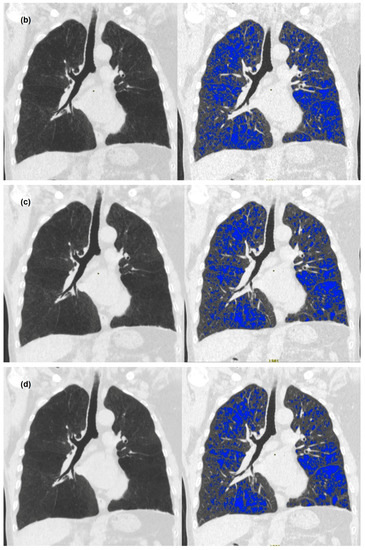

3. Results

3.2. Quantitative Measurements of Standard-Dose and Ultra-Low-Dose CT

4. Discussion